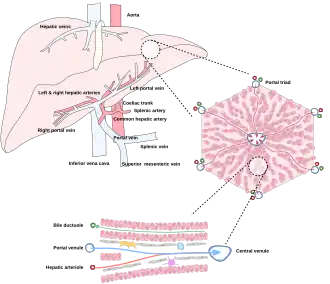

The liver is connected to two large blood vessels: the hepatic artery and the portal vein. The hepatic artery carries oxygen-rich blood from the aorta via the celiac trunk, whereas the portal vein carries blood rich in digested nutrients from the entire gastrointestinal tract and also from the spleen and pancreas.[11] These blood vessels subdivide into small capillaries known as liver sinusoids, which then lead to hepatic lobules.

Hepatic lobules are the functional units of the liver. Each lobule is made up of millions of hepatocytes, which are the basic metabolic cells. The lobules are held together by a fine, dense, irregular, fibroelastic connective tissue layer extending from the fibrous capsule covering the entire liver known as Glisson's capsule after British doctor Francis Glisson.[4] This tissue extends into the structure of the liver by accompanying the blood vessels, ducts, and nerves at the hepatic hilum. The whole surface of the liver, except for the bare area, is covered in a serous coat derived from the peritoneum, and this firmly adheres to the inner Glisson's capsule.

Microscopically, each liver lobe is seen to be made up of hepatic lobules. The lobules are roughly hexagonal, and consist of plates of hepatocytes, and sinusoids radiating from a central vein towards an imaginary perimeter of interlobular portal triads.[24] The central vein joins to the hepatic vein to carry blood out from the liver. A distinctive component of a lobule is the portal triad, which can be found running along each of the lobule's corners. The portal triad consists of the hepatic artery, the portal vein, and the common bile duct.[25] The triad may be seen on a liver ultrasound, as a Mickey Mouse sign with the portal vein as the head, and the hepatic artery, and the common bile duct as the ears.[26]

Blood supply

The liver gets its blood supply from the hepatic portal vein and hepatic arteries. The hepatic portal vein delivers around 75% of the liver's blood supply and carries venous blood drained from the spleen, gastrointestinal tract, and its associated organs. The hepatic arteries supply arterial blood to the liver, accounting for the remaining quarter of its blood flow. Oxygen is provided from both sources; about half of the liver's oxygen demand is met by the hepatic portal vein, and half is met by the hepatic arteries.[46] The hepatic artery also has both alpha- and beta-adrenergic receptors; therefore, flow through the artery is controlled, in part, by the splanchnic nerves of the autonomic nervous system.

Blood flows through the liver sinusoids and empties into the central vein of each lobule. The central veins coalesce into hepatic veins, which leave the liver and drain into the inferior vena cava.[47]

Diagram of liver, lobule, and portal tract and their inter-relations